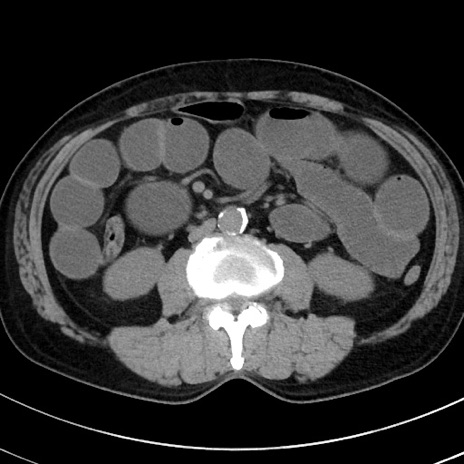

症例38(横断像)

【症例】70歳代 男性

【主訴】腹痛・嘔吐

【現病歴】昨晩より、嘔吐・腹痛あり。今朝になっても嘔吐あり。来院。

【既往歴】心臓バイパス手術、開腹胆摘、腸閉塞

【身体所見】BP 107/71mmHg、HR 116/min、腹部:平坦、軟、下腹部に軽度圧痛あり。反跳痛なし。

【データ】WBC 15100、CRP 0.32